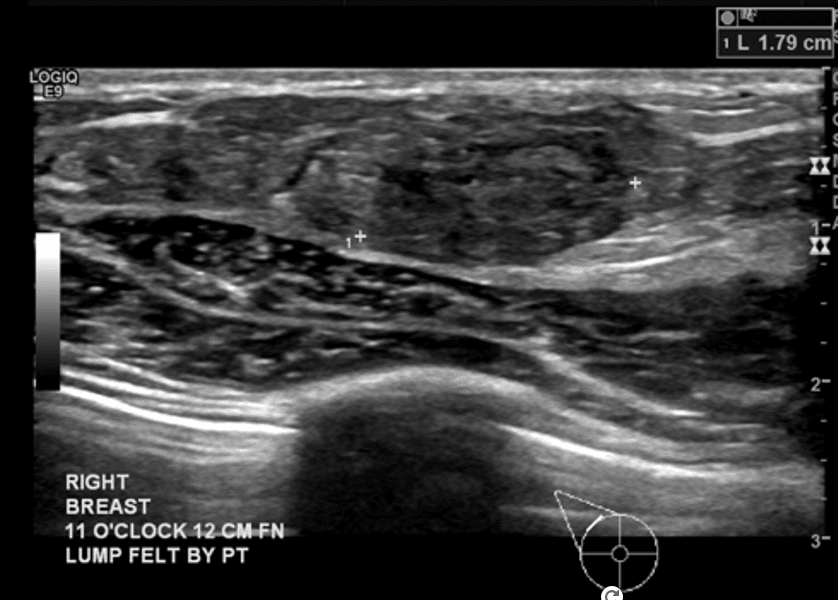

Lactating Adenoma

Lactating adenomas are benign (non-cancerous) masses comprised of dense glandular tissue and most commonly occur in the upper outer part of the breast. They can present during pregnancy or lactation and likely are related to hormonal stimulation. They may become large; however, they reduce in size as a woman progresses further in the postpartum period and eventually disappear when lactation is complete. They can appear similar to fibroadenoma on breast imaging, as smooth, oval lesions. Diagnosis can be confirmed with a core needle biopsy, but they do not require surgical excision.